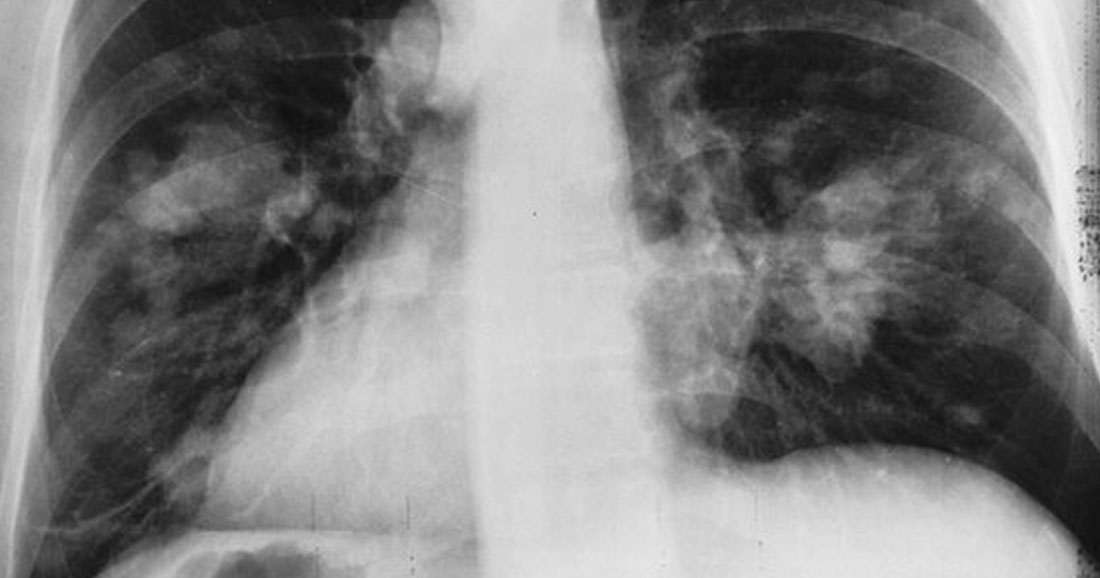

Le cancer du poumon est l’un des principaux cancers qui sévissent en France mais également l’un des plus meurtriers. En 2017, sur les 49 000 personnes atteintes d’un cancer du poumon, 31 000 en sont mortes. Ce nouveau traitement découvert par les chercheurs pourrait bien sauver de nombreuses vies.

Généralement, pour soigner les personnes atteintes du cancer du poumon avec métastase, on utilise depuis 2017 le Keytruda, un médicament d’immunothérapie (médicament qui facilite l’action des défenses immunitaires en détruisant l’enveloppe derrière laquelle les cellules cancéreuses se cachent pour mieux lutter face à la maladie). Ou bien le traitement classique à base de chimiothérapie qui vise à détruire directement les cellules cancéreuses. Mais des chercheurs ont eu l’idée d’associer ce médicament à la chimiothérapie classique pour soigner le cancer du poumon.

Les résultats parlent d’eux-mêmes. Le traitement a été testé sur un panel de 600 personnes, toutes atteintes du cancer du poumon. Un an après avoir reçu ce traitement, 70 % des patients parviennent à contrôler leur cancer ce qui permettrait de réduire de moitié les décès liés à ce cancer. Une grande avancée pour la lutte contre le cancer.